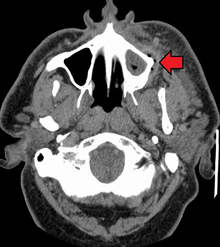

.jpg)

In certain cases, endodontic therapy may be necessary for the restoration of a tooth.[116] Endodontic therapy, also known as a "root canal", is recommended if the pulp in a tooth dies from infection by decay-causing bacteria or from trauma. In root canal therapy, the pulp of the tooth, including the nerve and vascular tissues, is removed along with decayed portions of the tooth. The canals are instrumented with endodontic files to clean and shape them, and they are then usually filled with a rubber-like material called gutta percha.[117] The tooth is filled and a crown can be placed. Upon completion of root canal therapy, the tooth is non-vital, as it is devoid of any living tissue.